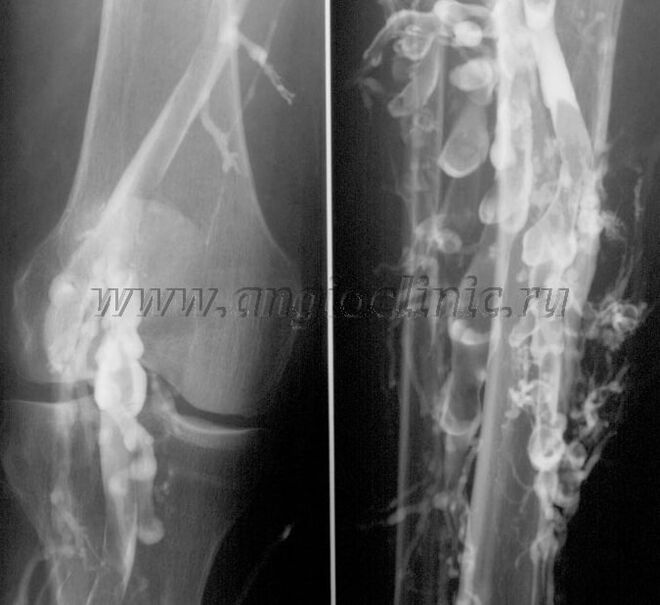

Phlébographie de contraste

Habituellement, l'échographie suffit pour un diagnostic complet de pathologie veineuse, mais dans certains cas, il est nécessaire d'étudier la relation entre l'état du système veineux profond et superficiel, notamment en cas de rechutes de varices et de varices secondaires.

Pour résoudre ces problèmes, un examen radiographique avec contraste est utilisé. Les veines saphènes sont percées et un produit de contraste est administré. Le mouvement du contraste est observé sur le moniteur de l'appareil à rayons X et tous les tests et projections nécessaires sont effectués. Actuellement, la phlébographie des varices est très rarement utilisée.